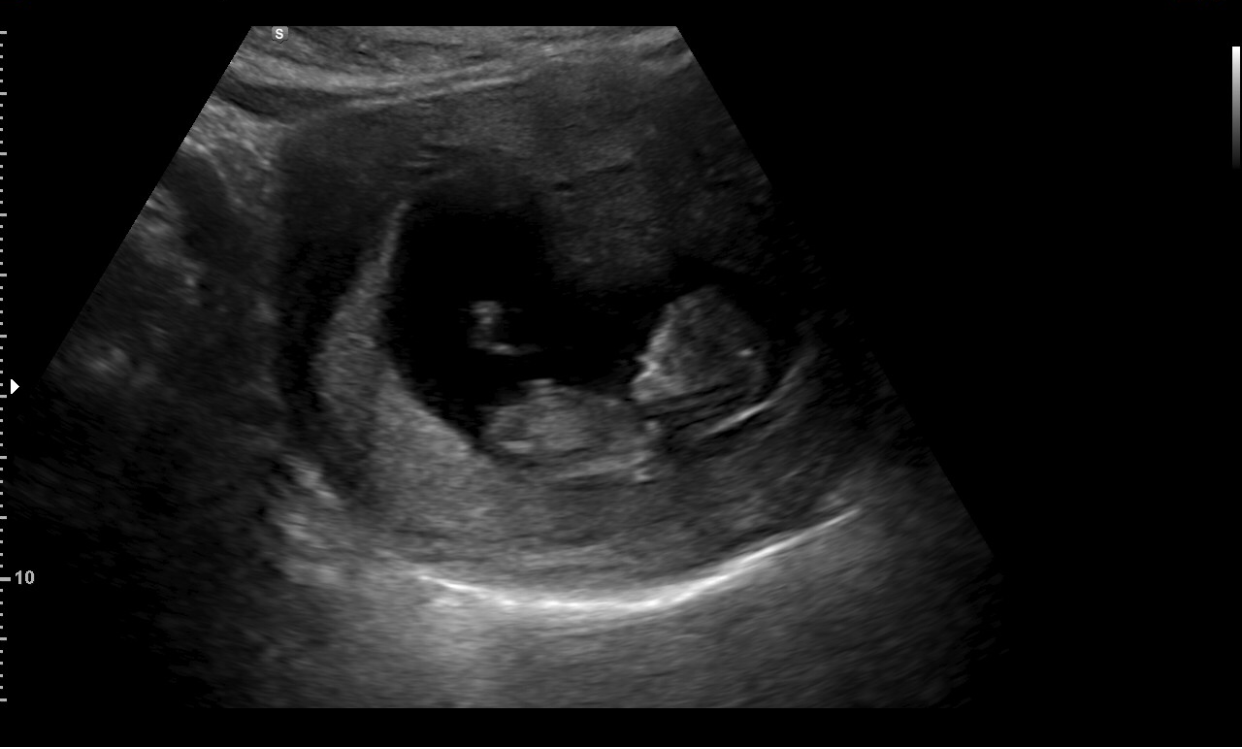

Het bloedverlies dat ik de paar dagen voor mijn 12-weken echo had, is een teken van een ‘miskraam in wording’ wist mijn verloskundige mij te vertellen nadat ze op de echo een lege embryo zag. Wist ik veel wat me te wachten stond. Een buitenbaarmoederlijke zwangerschap was misschien wel het heftigste dat ik ooit had meegemaakt. Dat zou dit niet zijn. Destijds had ik een dermate bloedverlies dat alle alarmbellen af gingen. Deze keer verwachte ik een natuurlijke menstruatie, al bleek dit toch even anders te zijn. Hoe stom had ik kunnen zijn om in mijn eentje met drie jongen bandito’s weg te gaan. Een miskraam bij 12-weken had ik nooit eerder ervaren…